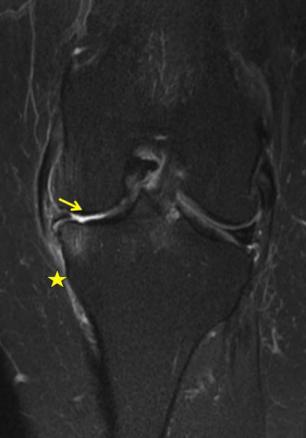

IRM du genou gauche pour une gonalgie gauche interne. Lésions dégénérative et luxation latérale du segment moyen du ménisque interne gauche avec disparition complète du cartilage tibial et condylien interne (flèche jaune. À noter, une ténosynovite des tendons de la patte d’oie (astérisque jaune).